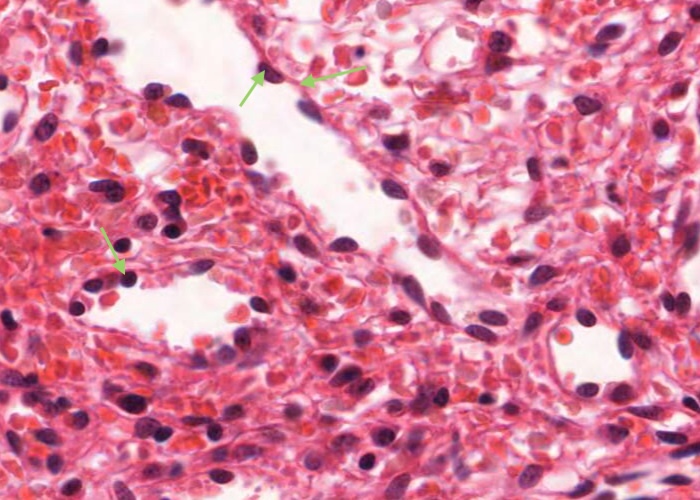

The important specializations of this vasculature are the tall postcapillary venules (TPCV), also called high endothelial venules (HEV). These vessels are lined by specialized cuboidal epithelium, look for an oval shaped nucleus (sometimes even described as columnar) instead of the usual squamous variety. They are located in the paracortex as the first segments of the venules.

Recall their role in the pathway of lymphocyte circulation. See if you can find several examples and even some sectioned transversely (see next item). If not, you will have no problem recognizing them if you go back and re-examine the section of the tonsil.

In this image, the tall postcapillary venule (TPCV), also called a high endothelial venule (HEV), is sectioned transversely. Look for an oval shaped nucleus (sometimes even described as columnar) instead of the usual squamous variety.

Some lymphocytes live for a very long time and so recirculate continuously. Their "homing behaviour" is a consequence of molecules on their cell surface interacting with complementary molecules on the endothelial cell surface of these specialised venules.